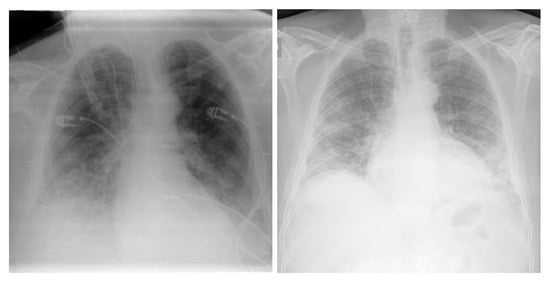

3.4.1. NIH Dataset

3.4.2. COVID-19 Image Data Collection

3.4.3. COVID-19 Radiography

3.4.4. BIMCV COVID19+

3.4.5. Montfort Dataset